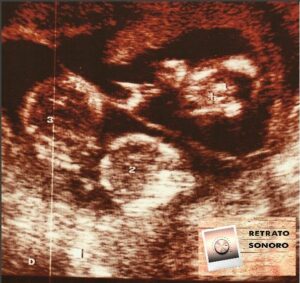

Vuelvo con el podcast. Vuelvo con Esteban y la foto escogida de la que te quiere hablar. Una ecografía de sus primeros hijos, sus trillizos. Esteban Liñares te cuenta cuando su mujer, Ángeles, trajo al mundo a tres niños. No uno primero, luego al cabo de meses o años otro y finalmente tras otros tantos meses o años el tercero, no. Ángeles se... Leer más »

La entrada Esteban y los trillizos que le regaló Ángeles. aparece primero en Retrato Sonoro.